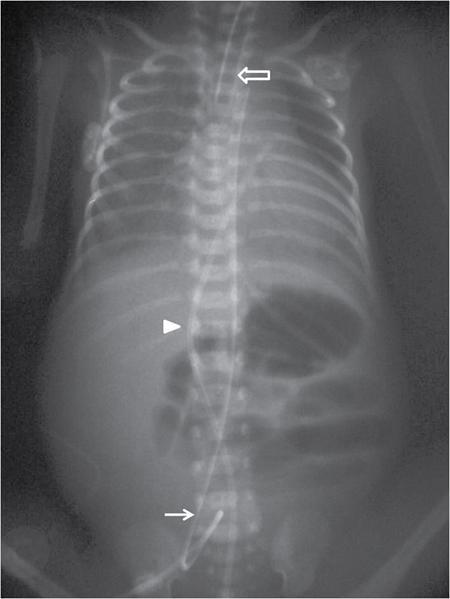

MISCELLANEOUS PAEDIATRIC RADIOGRAPHY – TECHNIQUES AND INTERPRETATION: SKELETAL SURVEY Padma V. Badhe The skeletal survey, generally performed in children, is a set of radiographs done in order to evaluate the entire skeleton. A skeletal survey, commonly used to evaluate skeletal dysplasias, acquired metabolic disorders and suspected child abuse, is still the key radiological investigation for the same. Hence, an explicit understanding of the technique along with the common disorders forms the basis of making a diagnosis in these paediatric pathologies. A skeletal survey is done for various skeletal dysplasias, non-accidental injury (battered baby syndrome) and suspected child abuse. It can also be done in cases of metabolic bone diseases, disseminated infections, multiple myeloma, eosinophilic granuloma. It is also used in evaluation of metastatic bone diseases and polyarticular arthropathy. Orthogonal views of the skull, spine, pelvis and one extremity are taken, preferable in standing position. For preterm babies/newborns, AP and lateral views of babygram may be taken. Projections: For skeletal dysplasias: Additional views: Both extremities may be taken if epiphyseal abnormalities and limb asymmetry is present. Focused views for specific pathologies may be taken. When a diagnosis remains uncertain, 1 year follow up is usually recommended. For preterm babies/newborns: AP and lateral views of babygram may be taken with additional specific views for extremities. For suspected non-accidental injury (NAI): AP and oblique view of chest is taken for better evaluation of the ribs. AP view of abdomen with pelvis. Both upper and lower limbs are evaluated. In lower limbs, two projections in AP and lateral (one with both femur including hip and knee joints; and another for foot and ankle) is taken. AP and lateral views of whole spine, skull. Oblique view of hands. A babygram should be avoided in cases of NAI, as subtle fractures are easily missed. Proper legal documentation while taking the views is very important and ideally two health care professionals must be present. For metabolic disorders: entire skeletal survey is usually not required. Specific views of hands, knees and spine may be taken with additional views depending on the suspected pathology. Centring point: Varies according to the part being examined. Angulation, collimation and orientation: Varies according to the part being examined. Images must be well collimated to obtain lower radiation dose. Detector size: Varies according to the part being examined: 8″ × 10″, 10″ × 12″, 11″ × 14″. Exposure: Ideally high kVp images are taken to reduce radiation dose. But in suspected NAI, low kVp/high mA images are recommended to better demonstrate findings. SID (Source Image Distance):100 cm Grid: Grids are not routinely used to image spine, pelvis, skull and abdomen in children. Radiation dosage: 0.3–3 mSv Essential image characteristics: Adequate spatial resolution, high signal to noise ratio, low kVp (50–70) for high contrast should be done. Excellent bone and soft tissue details are required. The presentation of skeletal dysplasia can range anywhere from minimal stunting of growth and bowing of limbs to severe dwarfism and multiple fractures. Knowledge of the commonly encountered dysplasias with an approach to arrive at a diagnosis is vital in any Radiologist’s practice The following flow chart summarizes the classification of important skeletal dysplasia: The following table summarizes the various dysplasias affecting the axial skeleton: TABLE 7.5.1.1 The following flow chart summarizes the working approach to skeletal dysplasias: Osteopetrosis (Albers-Schonberg disease/Marble bone disease) (Fig 7.5.1.1): Osteopetrosis clinically presents with anaemia/thrombocytopenia or cranial nerve compression. Radiological features include generalized increase in bone density with loss of medullary space. However, cortico-medullary appreciation with cortical thinning is also rarely seen. Bone within bone appearance with Erlenmeyer flask deformity is also noted. Pyknodysostosis (Figs. 7.5.1.2 and 7.5.1.3): patient presents with short stature. Unlike osteopetrosis, there is no anaemia. Radiographs show generalized increase in bone density with preserved medullary canal. There is mandibular hypoplasia with obtuse angle. Acro-osteolysis is also a feature. Dental caries with osteomyelitis of the jaw may be seen. Sclerosing dysplasia presenting as wavy undulating new bone formation. Usually monomelic, lower limb and along one side. The classic appearance is described as Dripping candle Wax sign. It is a Sclerosing dysplasia with radiological features of symmetric juxta-articular involvement in epimetaphyseal region. They are 1–10 mm in diameter and uniform in size. No metabolic activity is seen on bone scans. This skeletal dysplasia shows diffuse decrease in bone density with paper-thin cortex. Fractures heal in normal time but shows callus with poorly cellular matrix. Wormian bones and enlarged sinuses may be seen. Codfish vertebra (Biconcave vertebra) may be seen. Metaphyseal corner fractures are not seen in osteogenesis imperfecta that helps to differentiate it from battered baby syndrome. There are four types of OI out of which type one is most common (Figs. 7.5.1.6 and 7.5.1.7). The radiological features of MPS include Osteopenia and Universal platyspondyly. The intervertebral disc spaces are maintained. Proximal pointed metacarpals is an important radiological finding. Hurler’s syndrome show anteroinferior beaking with short and wide metacarpals. Varus deformity of humerus is characteristically seen in Hurler’s syndrome (Fig. 7.5.1.8). Mental retardation & corneal clouding is seen in Hurler’s syndrome whereas these Hunter’s disease has normal intelligence with no corneal clouding. Morquio’s syndrome shows central beaking (Fig 7.5.1.9). This skeletal dysplasia shows normal bone density with rhizomelic limb shortening and normal trunk. Narrowing of spinal canal is classically seen with decrease in the Interpedicular distance caudally. Other radiological features include trident hand (separation of middle & third fingers), Champagne glass pelvis (short, flat ilia and small sciatic notch), bullet nose vertebra and overexpansion of skull with narrow foramen magnum (Fig. 7.5.1.10). This skeletal dysplasia is characterized by normal bone density with dwarfism and normal craniofacial skeleton. The interpedicular distance is normal. There is severe platyspondyly with anterior tonguing (disappears at older age). Other radiological features include increased disc space, short stubby metacarpals, small irregular epiphysis and widened metaphysis. Anterior tonguing is a feature of Pseudoachondroplasia. This form of skeletal dysplasia involves the spine and epiphyses (Fig. 7.5.1.11). There is normal bone density with rhizomelia. Spine and Pelvis can be involved. Premature osteoarthritis can be seen. The other characteristic features include Platyspondyly and small irregular epiphysis. There are two forms Spondyloepiphyseal dysplasia Congenital and Spondyloepiphyseal dysplasia Tarda. Spondyloepiphyseal dysplasia Congenita is Autosomal dominant and shows pear-shaped vertebrae. Spondyloepiphyseal dysplasia Tarda is X Linked recessive with heaped up vertebrae. It has two forms. The first form is Conradi Hunermann syndrome which is autosomal dominant characterized by asymmetric limb shortening with metaphyseal flaring (Fig. 7.5.1.12). The Autosomal recessive form is Fatal in first few years. Rickets: Rickets refers to deficient mineralization of the growth plate in the paediatric population due to deficiency of vitamin D. In an immature skeleton, there is abnormal mineralization at the zone of provisional calcification in the metaphysis due to osteoid deposition resulting in widening of the growth plate. The features of rickets include fraying, splaying and cupping (Fig. 7.5.1.13). Fraying denotes indistinct margins of the metaphysis whereas splaying denotes widening of metaphyseal ends. Term ‘Cupping’ is used for increased concavity of the metaphysis. These findings are typically seen involving areas of active growth (e.g. distal femur and proximal tibia in the knee) Bowing is a result of associated osteomalacia leading to weakening of weight-bearing lower limb bones. Other bone deformities such as genu valga, genu varum, protrusio acetabuli can also be seen. The lower ribs may also be drawn inwards inferiorly by the attachment of the diaphragm this is called Harrison’s sulcus. Scurvy: Scurvy is a result of dietary deficiency of Vitamin C (ascorbic acid). The classic presentation is that of a patient with an increased bleeding tendency and osteopenia with poor wound healing. Features of scurvy include generalized osteopenia with cortical thinning termed as ‘pencil-point’ cortex. Other radiological findings include the periosteal reaction due to subperiosteal haemorrhage. Expansion of the costochondral junctions occurs forming scorbutic rosary. Bleeding into the joint spaces may result in hemarthrosis. Circular, opaque radiologic shadow surrounding epiphyseal centres of ossification may result from bleeding (Wimberger ring sign) (Fig. 7.5.1.14). Frankel line may be seen. It represents dense zone of provisional calcification. Lucent metaphyseal band is seen underlying Frankel line called as Trümmerfeld zone. Metaphyseal spurs may be seen that result in cupping of the metaphysis (Pelkin spur). Pelkin fracture (metaphyseal corner fracture) can also be seen. Images obtained must be of good resolution with adequate bone and soft tissue details. Additional views: They have already been described in positioning. CT Brain in can be done in cases of NAI to look for subdural hematomas. A skeletal survey is the first-line imaging modality for evaluation of skeletal dysplasia, nonaccidental injury and metabolic bone diseases. The skeletal survey must be tailored according to the respective indication. It helps to characterize syndromic patterns in skeletal dysplasias, with evaluation of complications. In cases of diagnostic dilemmas, additional focused view and occasionally yearly follow-up is recommended. A high index of suspicion is needed in utilizing skeletal survey as a diagnostic modality in NAI. At the same time, one must also remember the legal and social implications of making this diagnosis. BABYGRAM Babygram is a colloquial term used for a radiograph of the whole body of a newborn or just the chest and abdomen (thoracoabdominal babygram) on a single image. As the name suggests it is a rather non-targeted study. It is most commonly requested after line placement. Evaluation of skeletal abnormalities in a deceased foetus is typically performed using anteroposterior and lateral views of a babygram. It helps in pointing out skeletal causes of death in stillborn or dead foetuses. This will help the treating physician and parents understand the reason for baby’s death. This will also help in future genetic counselling of the couple. Sometimes chest or abdominal radiographs of the baby are requested but due to radiographers error or inexperience with small babies, there is inclusion of the region not to be assessed leading to a false babygram. Babygram is most frequently done after line placement in neonates, to view the position of the umbilical vein or artery catheter and to confirm appropriate placement. It is a useful modality in skeletal dysplasias (Fig. 7.5.1.15) like osteogenesis imperfecta, thanatophoric dysplasia and chondrodysplasia punctata. It can also be used for skeletal deformations probably caused by foetus akinesia and in cases of Caudal regression syndrome. In stillborn foetuses, it is used for evaluation of skeletal dysplasias prior to an autopsy (Fig. 7.5.1.16). It is also used in screening for surfactant deficiency and in cases of Necrotizing Enterocolitis in preterm babies where it can help to see the bowel dilatation, intramural and portal venous gas. It can be done in aneuploidies like trisomy 18 and in cases of sudden infantile death syndrome. All the essential equipment and room need to be prepared including the exposure factor. This should be done prior to placing the baby on the table to prevent any neonatal heat loss. Ensure that the baby is correctly identified. Give brief explanation to the patient’s parents regarding the procedure, its risks and benefits. Ensure that the accompanying relative is not pregnant (if female). Parents/guardians/nurses should be instructed to hold the baby with arms above the head and legs straight down. Sandbags/tapes can be used to immobilize the baby. Avoid taking the radiograph when baby is crying. Normal appearance: The endotracheal tube should lie in the lower third of trachea, distance can vary with position of baby’s head. Umbilical artery catheter has an inferior dip along the internal iliac artery, which then turns superiorly along the aorta. The tip should lie in the mid-thoracic aorta (T6–T10) or lower (L3–L4) away from aortic branches to prevent any thrombosis. Umbilical venous catheter does not have the inferior curvature, but rather a posterolateral angulation to the right near the liver through the ductus venosus. The tip should lie in the superior IVC or right atrium at T8/T9 vertebral level (Fig. 7.5.1.17). Portal venous gas may be seen initially after insertion. In a stillborn foetus, the approximate gestation age of the foetus and corresponding ossification centres must be known. In early gestation, the lack of appearance of an ossification centre may be mistaken for skeletal dysplasia. Both chest and abdomen should be included. In a rotated patient, the distance between the spinous process to medial end of clavicles will be asymmetric. The medial end of clavicle should overlap the lung apex, if above, suggests lordotic image. Motion artefacts to be reduced as much as possible. A crying neonate may result in an expiratory film, and hence must be evaluated accordingly. In evaluation of skeletal dysplasias in the newborn, additional views of skull and hand have to be obtained. Baby gram is a useful diagnostic investigation for position of the paediatric umbilical catheters. It helps in general survey in skeletal dysplasia (Fig. 7.5.1.18). It is a simple, effective study in deceased foetus for diagnosis and further counselling, sometimes obviating the need for an autopsy. As baby gram is a non-targeted study, it increases the dose of radiation for the baby. As the exposure settings remain same for the entire body of the baby, the quality of the image decreases. This increases the chances of missing subtle findings. The babygram in a neonate is currently used to localize umbilical catheters. In stillborn fetuses, it is still an important study for documenting and confirming skeletal dysplasias. Understanding the normal appearance as per gestation age and patterns of various common skeletal dysplasias is essential for evaluation. Being a non-targeted study, it should not be used as an alternative study to evaluate the chest or abdomen considering radiation exposure and poorer image quality. INVERTOGRAM Invertogram was first described by Wangensteen and Rice in 1930. It was used as a first investigation to be ordered in evaluation of infants with clinically diagnosed or suspected Anorectal Malformation (ARM). ARM is a serious but surgically treatable congenital malformation with approximate incidence of 1 in 5000 live births. Though the diagnosis of this condition is based on clinical history and physical examination, imaging plays an important role in deciding the type of ARM, and associated complications to aid in management. International classification of anorectal malformations is as follows. Syndromic association is seen as a part of VACTERL defects, trisomy 21 13 and 18, Klippel Feil syndrome, cat eye syndrome etc. The main indication of Invertogram is to evaluate anorectal malformation in a neonate. A radio-opaque marker is placed over the external anal opening. Infant is held inverted by holding both thighs, maintaining this posture for at least 5 minutes before taking an X-ray in true lateral position (Fig. 7.5.1.19). Exposure is made during inspiration. The Invertogram should ideally be done 24 hours after birth as, the rectal gas may not reach the terminal segment if study is done too early. Pubo-coccygeal line (PCL) is drawn from upper border of pubic symphysis (which corresponds to centre of pubic bone on lateral X-ray) to sacrococcygeal junction. I point is the inferior most point of ischial ossification centre. A line which is drawn parallel to PC line passing through the I point is called I line. ‘A’ point is represented by marker placed at anal pit. The position of rectal pouch gas shadow is observed with respect to these lines and appropriate diagnosis is made (Fig. 7.5.1.21). A diagnosis of high ARM is made when gas shadow of rectal pouch is cranial to PCL. If rectal pouch gas shadow is in between PCL and I line, it is called as intermediate ARM and if it is caudal to I line, it is diagnosed as low ARM. Gas in urinary bladder or vagina or beaking of gas shadow of rectal pouch indicates fistula into one of these sites. Associated congenital abnormalities like spinal defects are also looked for in the invertogram (Fig. 7.5.1.22). Invertogram done too early (less than 24 hours) may not demonstrate rectal gas. Meconium plugging the terminal segment gives false position of the rectal gas. Positioning can cause discomfort to child and an irritated crying child actively contracts the sphincter muscles, pushing the gas shadow higher. Rectum may be pulled cephalad due to gravity in inverted position. The rectal gas may escape through an associated fistula. Erroneous interpretation can also occur due to sacral anomalies and when gas in vaginal cavity is misinterpreted as distal rectal gas. Both ischial bones should superimpose and terminal blind loop should be well distended. It is an easily available modality and can be done quickly, does not require additional equipment. It has lesser radiation dose as compared to CT invertogram. It provides a rough guide as to the type of ARM and decides management. Higher localization of obstruction due to various causes like meconium plugging, imaging done too early etc. as described above in pitfalls. It is more uncomfortable to the baby as compared to the prone cross-table lateral view, and a crying baby contracts the puborectalis leading to erroneous results. K. L. Narasimharao et al. modified the technique and proposed cross-table lateral view for evaluation of infants with ARM’s which has shown equal or better information and has now replaced invertogram (Fig. 7.5.1.23). Prone cross-table lateral view is considered equivalent or even better in determining the level of anomaly. Positioning is in this view is prone in genupectoral position (at least for 3 minutes). It is taken in true lateral and during inspiration. The lines used to delineate types of ARM is essentially the same as in an invertogram. It is preferred over invertogram as relatively easy positioning of the infant and less discomfort allows for better cooperation of neonate during the study. It also eliminates the effect of gravity. ARM with fistula is better delineated as, in an invertogram, fistula/gas is at the highest level and gas may escape through it. CT invertogram is another modality that delineates anatomy better but is rarely used. In the era of cross-section imaging, MRI and USG have opened new modalities for accurate diagnosis of ARM, but invertogram being readily available, inexpensive, quick and cost-effective is used as first investigation for evaluating a patient with suspected or confirmed case of ARM. Cross-table lateral view has replaced invertograms as it is more patient-friendly and equally effective. UPPER GASTROINTESTINAL SERIES Rushit S. Shah An upper gastrointestinal (GI) study is a radiographic examination of the GI tract from the pharynx to the ligament of Treitz after oral administration of contrast agent. The use of upper GI studies is gradually declining with the increasing availability of paediatric endoscopy and the challenge for the modern radiologist to work in conjunction with the surgeon and gastroenterologist to select the right patients for an upper GI series. However, the upper GI series remains the key for demonstrating many anatomical abnormalities. The upper GI series is also useful in evaluating gastro-oesophageal reflux in conjunction with 24 pH monitoring. The upper GI examination is useful in evaluating many conditions including but not limited to: